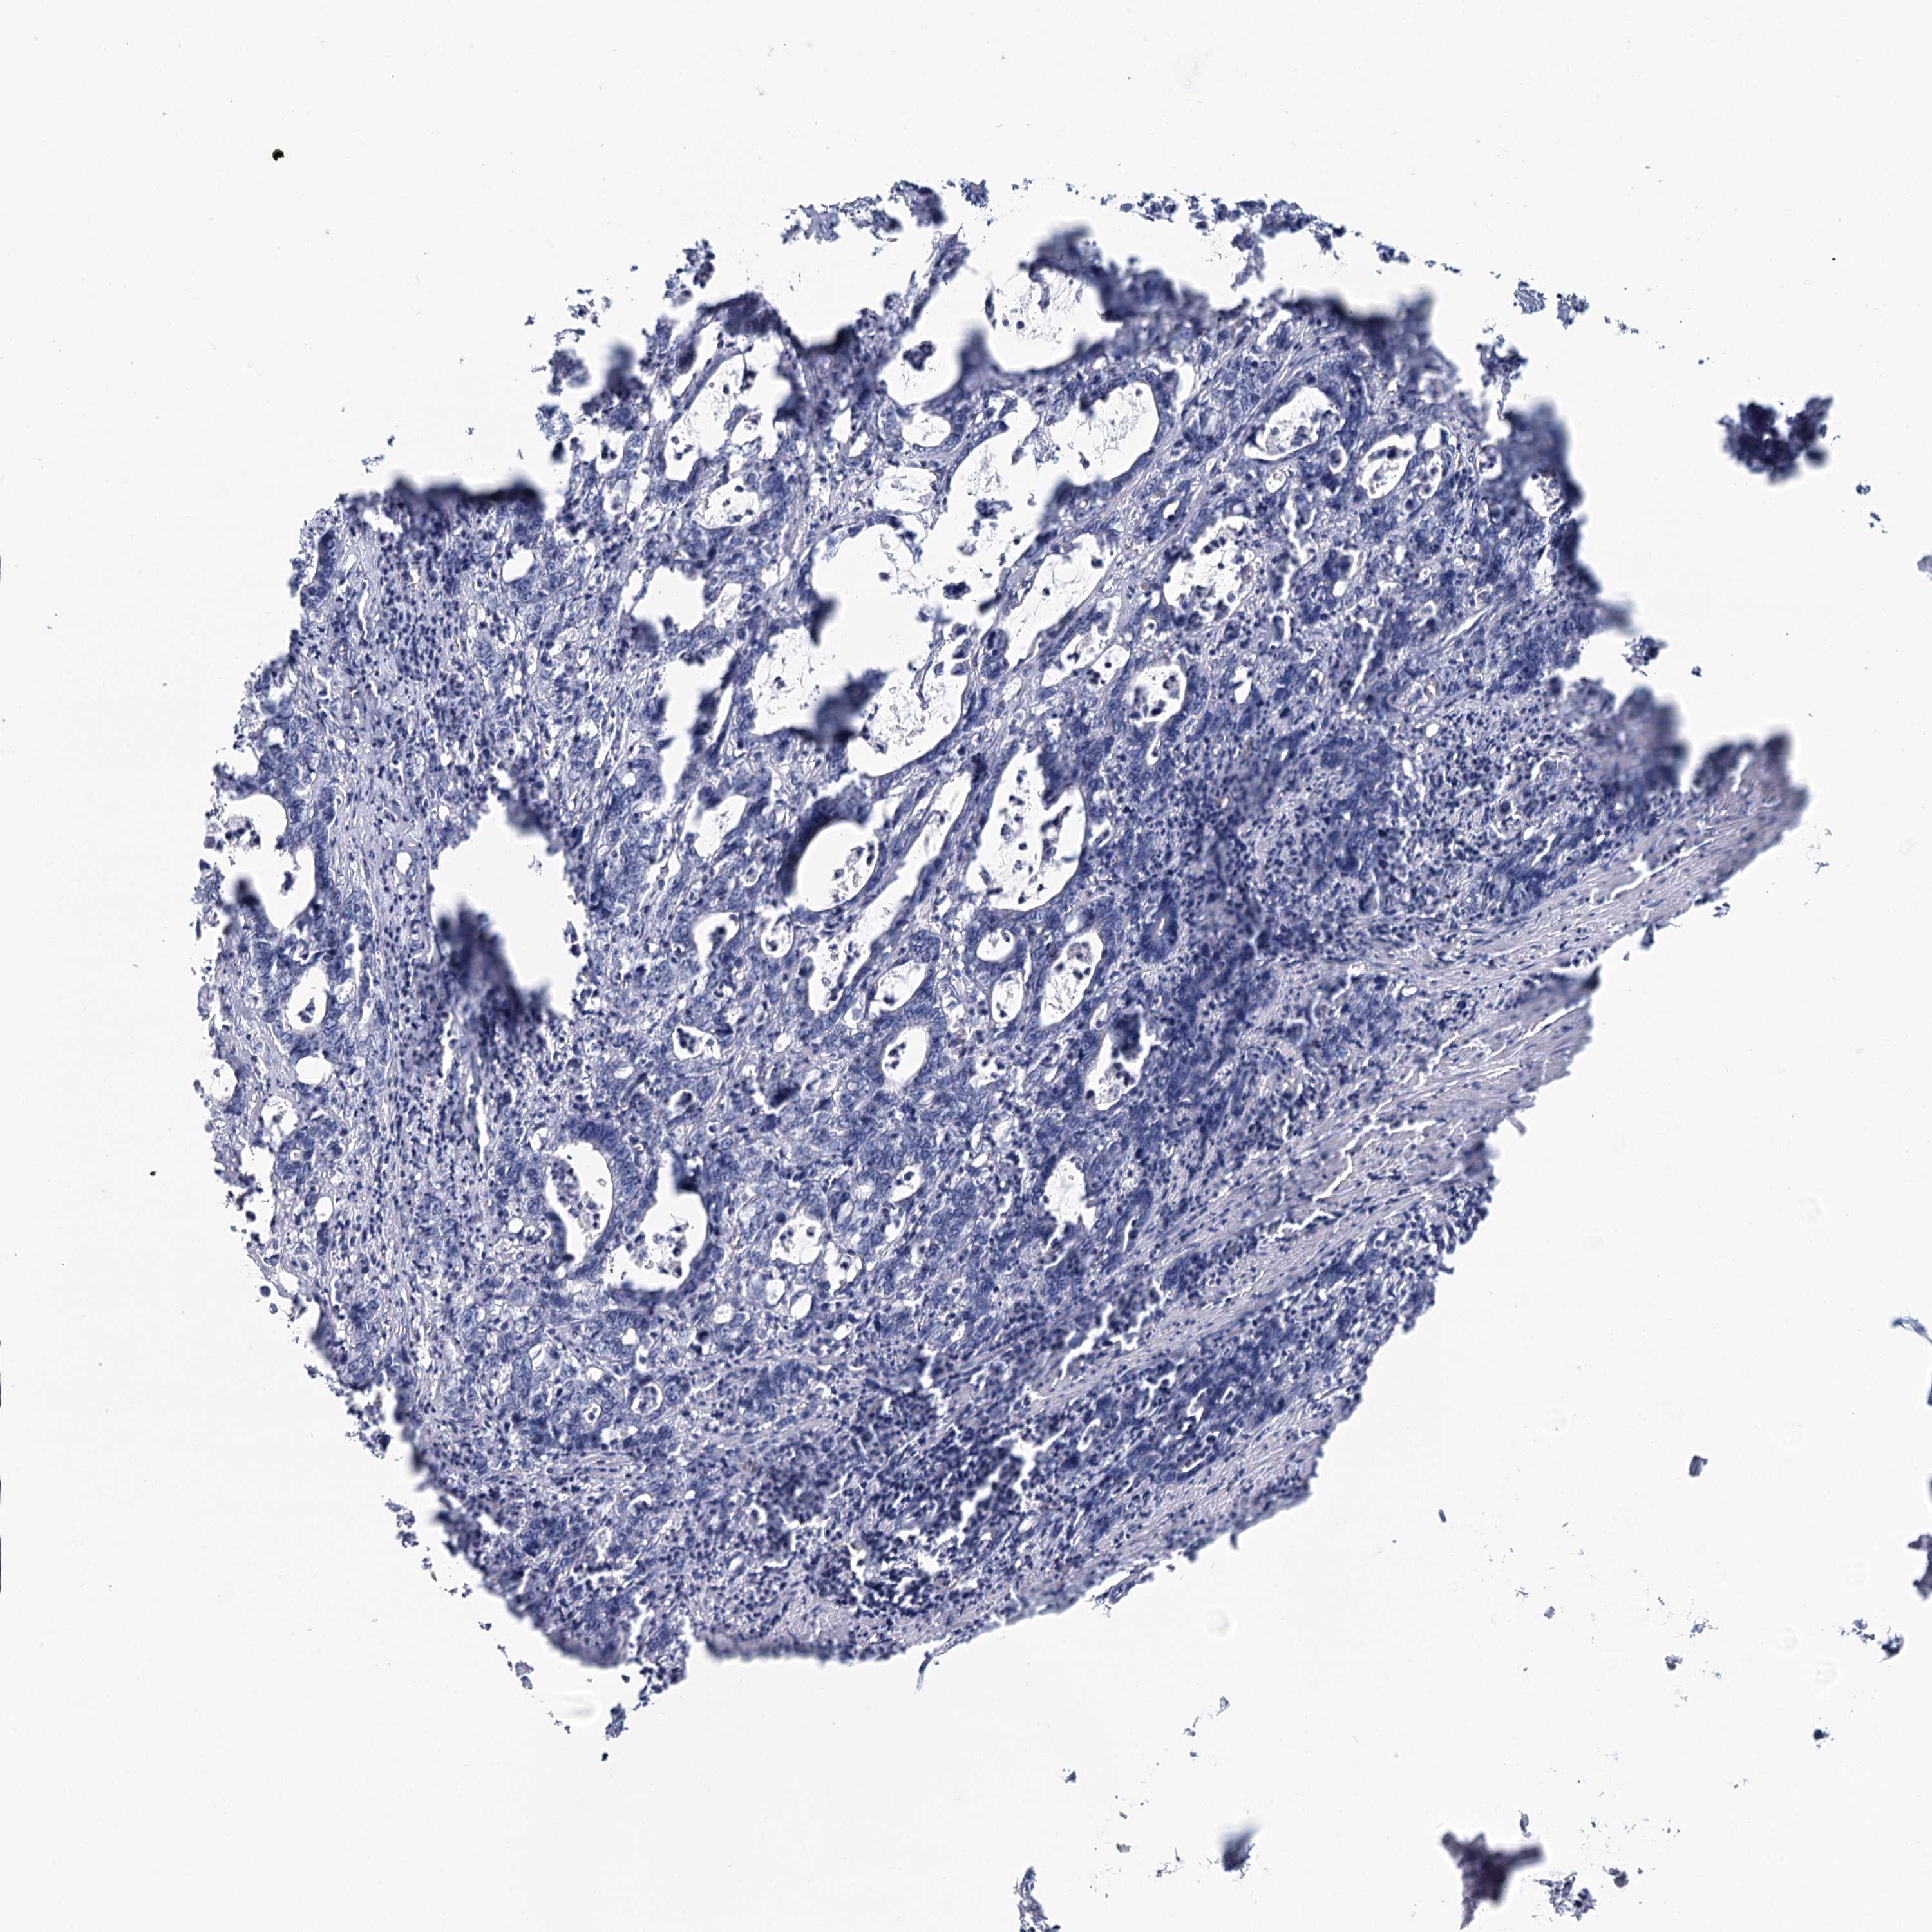

Colorectal cancer

Colon adenocarcinoma